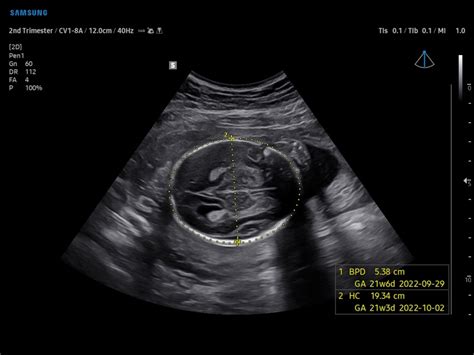

Alright, let’s get into the first acronym: IBPd . This stands for Biparietal Diameter , which is the measurement of the baby’s head. Specifically, it refers to the diameter of the head from one parietal bone to the other. Think of it like measuring the widest part of the baby’s head. The IBPd measurement is one of the key indicators used to estimate your baby’s gestational age and to assess head growth. This measurement helps determine if the baby’s head size is appropriate for its age. The IBPd is typically measured in millimeters, and the values are compared against a standard growth chart that shows the expected range for each week of pregnancy. Deviations from the expected range can sometimes indicate potential issues, such as macrosomia (a larger-than-average baby) or microcephaly (a smaller-than-average head). However, it is important to remember that a single measurement alone doesn’t tell the whole story. Your doctor will consider the IBPd in conjunction with other measurements and assessments.

HC: Deciphering Head Circumference

Next up, we have HC , which stands for Head Circumference . The HC measurement is the circumference of the baby’s head, which gives a comprehensive assessment of the head’s size. Like the IBPd, the HC is a critical parameter for monitoring fetal development. By measuring the HC, your doctor can gain more insight into the baby’s growth trajectory and identify any potential developmental issues. The HC measurement complements the IBPd, providing a more complete picture of the head’s dimensions and growth rate. This holistic approach helps to get a more accurate assessment of the baby’s well-being. So, let’s dig a bit deeper into what HC is all about.

Understanding the HC Readings